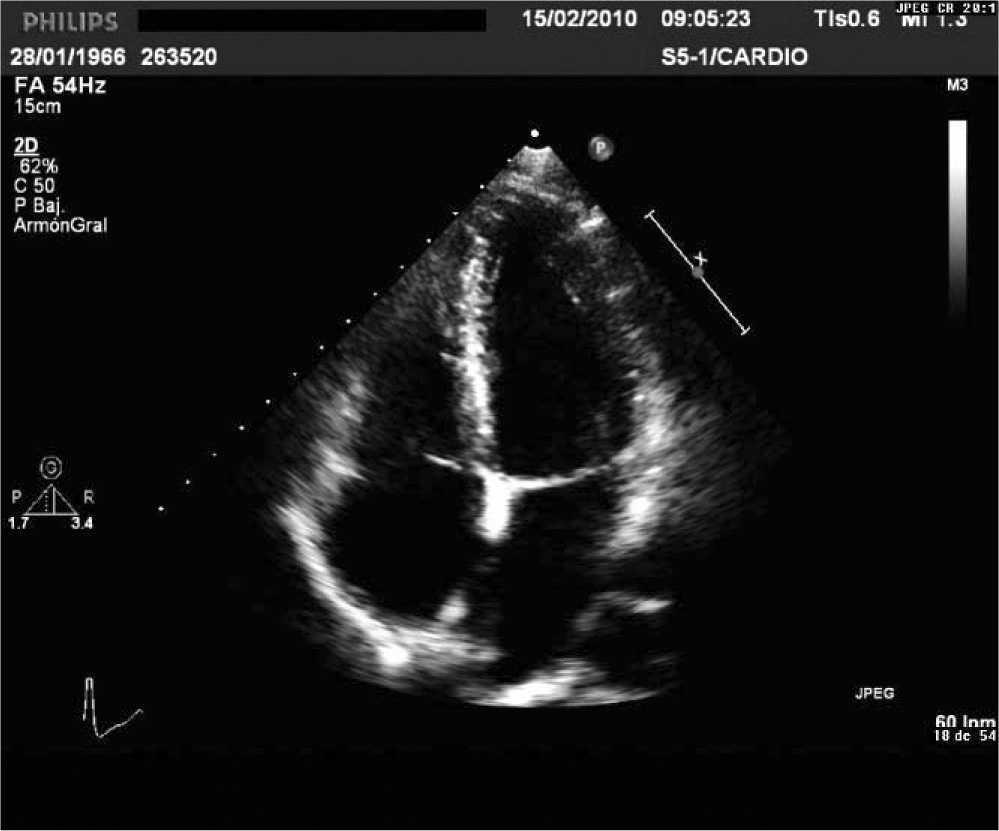

Ecocardiografia

É um exame de ultrassom do coração, simples, rápido e indolor, altamente eficiente para avaliar a função do coração, o tamanho, as válvulas, se há alguma sequela de infarto ou outras doenças cardíacas.